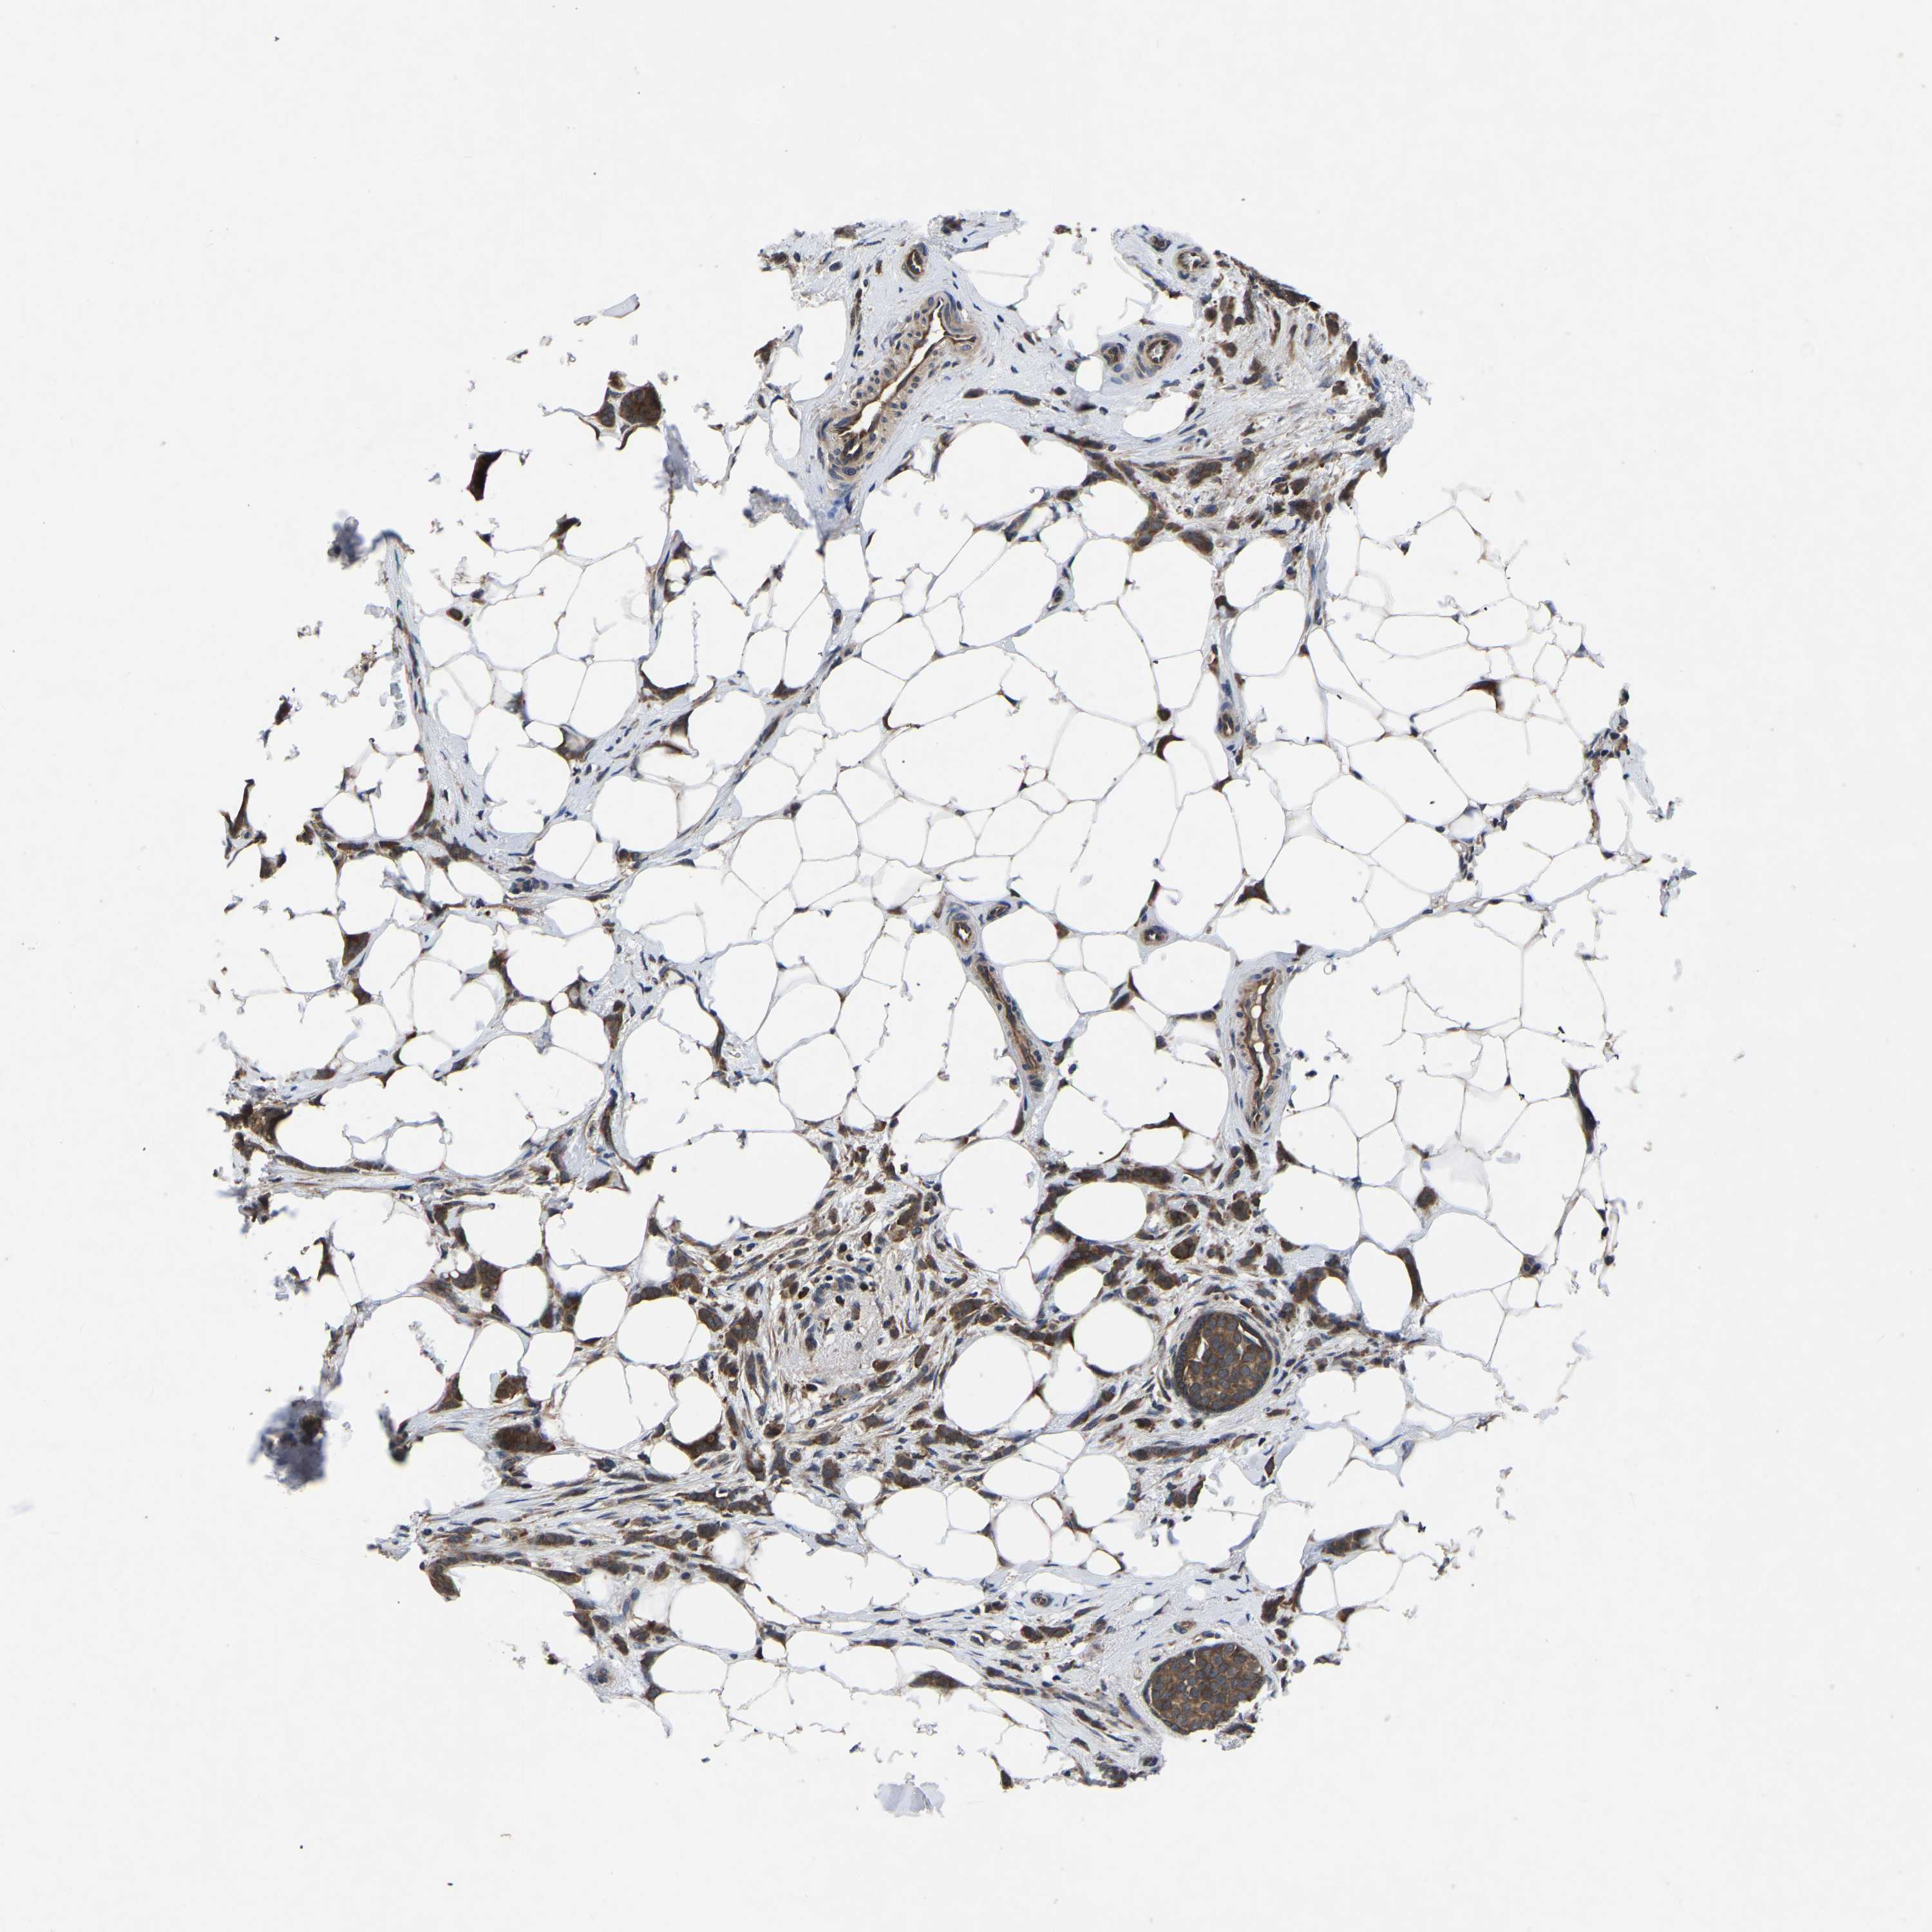

CANCER BREAST CANCER Show tissue menu

BRCA TCGA BRCA VALIDATION PROTEIN EXPRESSION

ANTIBODIES

AND

VALIDATION